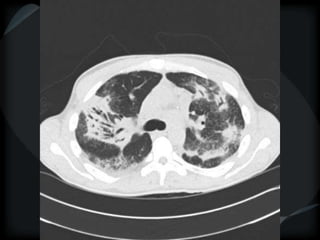

RETICULAR PATTERN - UIP

 peripheral reticular lines / inter and intralobular septae

 honeycomb

 Traction bronchiectasis

 None or minimal ground glass

 Gradient increasing from apex to base

 Skip areas

 Asbestosis = basilar – bands – pleural calcification